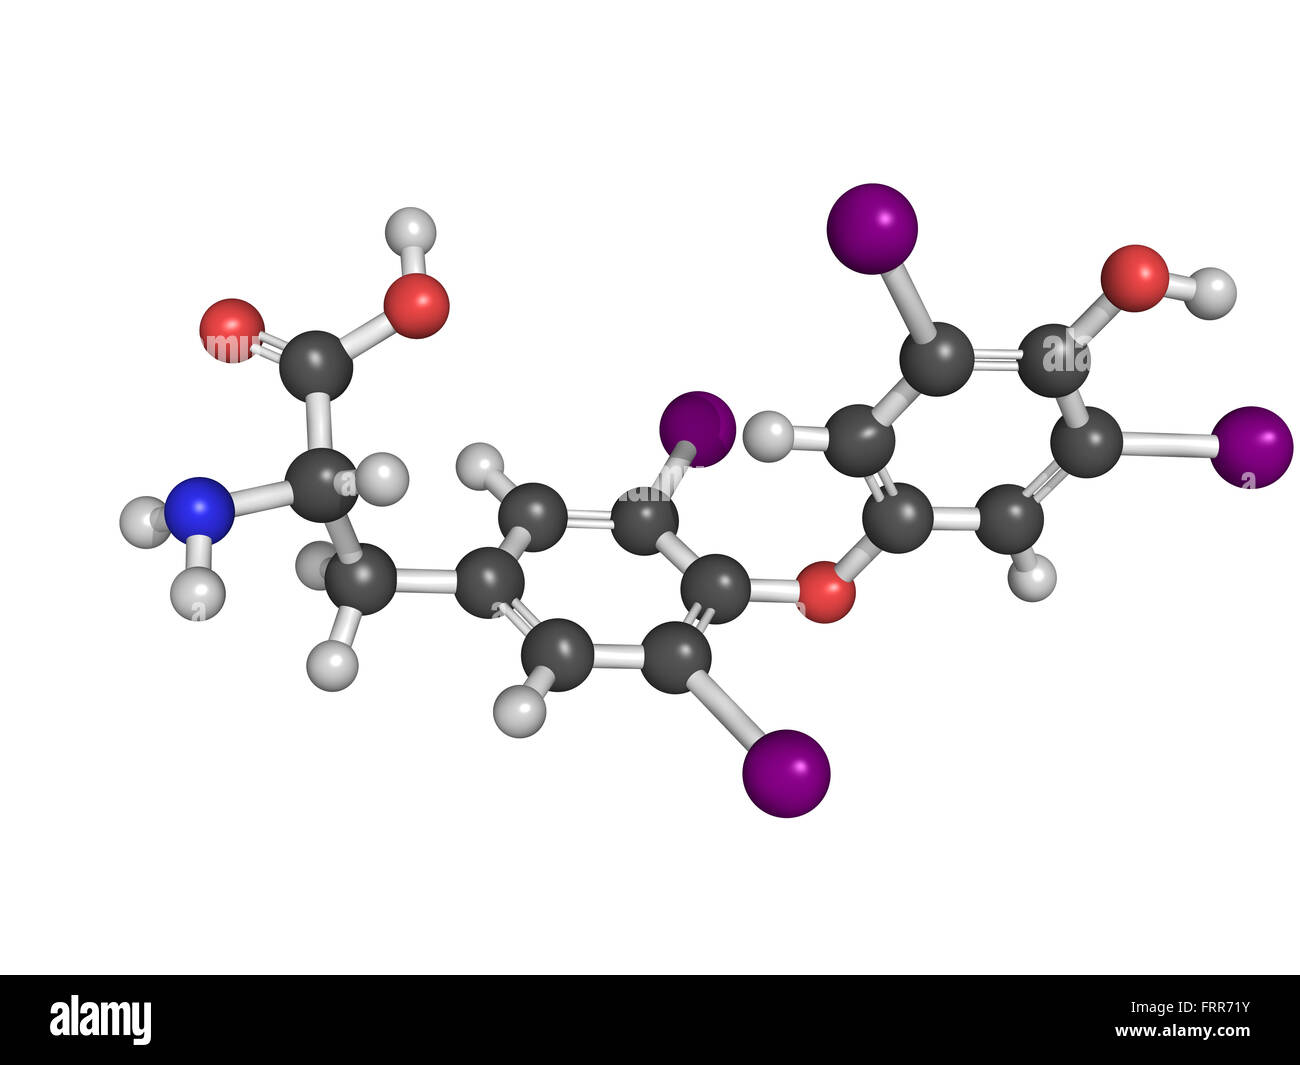

RFFRR720–La thyroxine hormone thyroïdienne molécule. Thyroxine est une hormone thyroïdienne qui joue un rôle dans le métabolisme de l'énergie règlement

RFFRR71Y–La thyroxine hormone thyroïdienne molécule. Thyroxine est une hormone thyroïdienne qui joue un rôle dans le métabolisme de l'énergie règlement